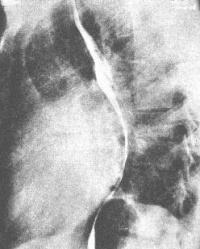

(一)X线检查 轻度二尖瓣关闭不全者,可无明显异常发现。严重者左心房和左心室明显增大,明显增大的左心房可推移和压迫食道。肺动脉高压或右心衰竭时,右心室增大。可见肺静脉郁血,肺间质水肿和KerleyB线。常有二尖瓣叶和瓣环的钙化。左心室造影可对二尖瓣返流进行定量。